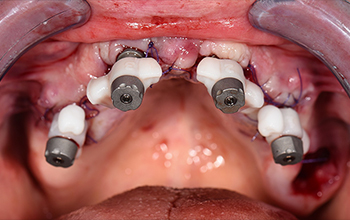

Après le retrait de l’ancien bridge métal-céramique, les dents restantes ont été extraites de manière atraumatique afin de préserver au maximum la paroi vestibulaire de l’os, ce qui est particulièrement important aux emplacements prévus pour la pose des implants. Quatre implants ont été posés immédiatement. Après la mise en place des piliers « multi-unit », une radiographie panoramique de contrôle a été réalisée avant la suture, afin de vérifier la position des implants ainsi que l’adaptation précise des piliers.

Fig. 03 : radiographie panoramique de contrôle a été réalisée avant la suture.

Immédiatement après la suture, des piliers de type « Scan-Transfer » de l’entreprise IPD, ont été placés sur les piliers « Multi-unit » (IPD propose des piliers « multi-unit » pour 25 marques d’implants dentaires et 80 plateformes différentes). Ceux-ci permettent une numérisation précise à l’aide d’un scanner intra-oral, selon un protocole spécifique qui évite toute distorsion de l’empreinte dans les zones édentées.